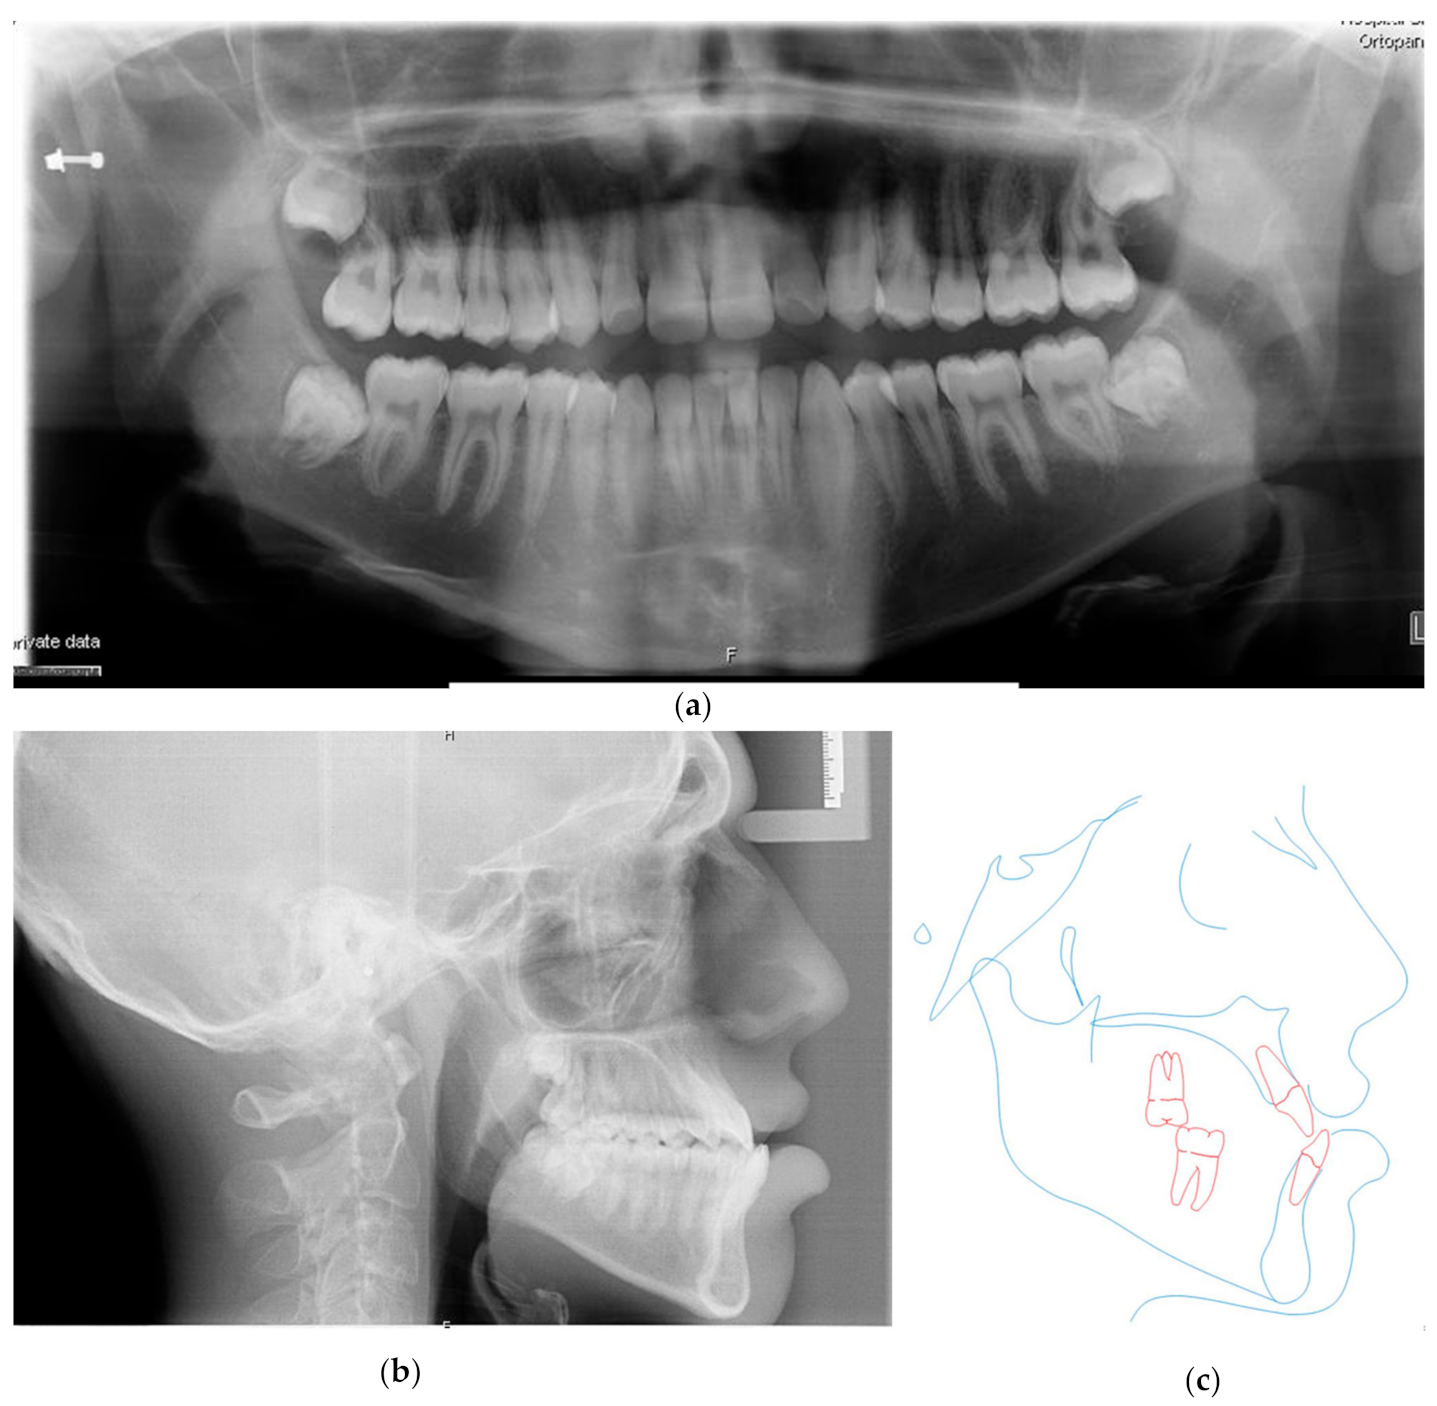

3.1. The Presurgical Orthodontic Treatment